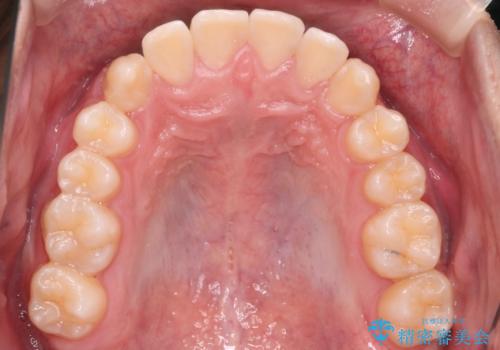

心配していた歯肉退縮も起こらず、前歯の噛み合わせと歯並びが綺麗に改善されました。

期間も1年2ヶ月と短期間で終了することができ、とても満足度の高い治療になりました。